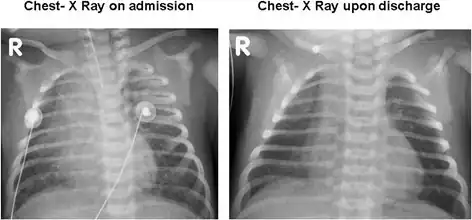

Bilateral patchy infiltrates due to pulmonary hemorrhage on admission and resolution upon discharge.

Bilateral patchy infiltrates due to pulmonary hemorrhage on admission and resolution upon discharge. -